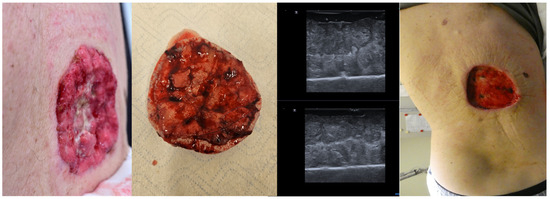

9. Ex Vivo Tumor Margin Assessment